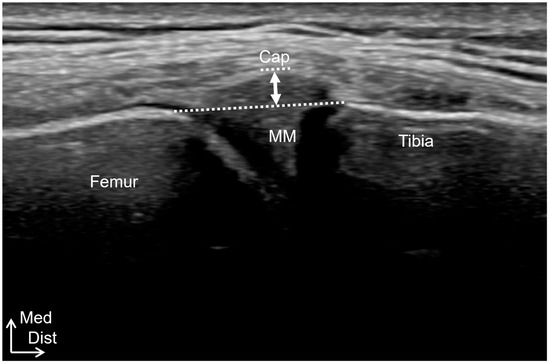

Ultrasound imaging was performed using a Noblus device (Hitachi Medical Systems, Tokyo, Japan) with an 18 MHz linear transducer in B-mode. MME was performed with the knee extended as much as possible, and the midportion of the medial meniscus was captured as a long-axis scan of the MCL. The vertical distance from the line segment connecting the medial end of the medial condyle of the femur and tibia, excluding the osteophytes, to the outer edge of the medial meniscus was calculated (Figure 3). Articular swelling was defined as a hypoechoic area at the suprapatellar porch, and joint effusion was measured as the maximum distance between the superficial and deep synovium.

Figure 3.

MME measurements. MME (white arrow) was measured as the vertical distance from the line segment connecting the medial end of the medial condyle of both the femur and tibia (white line), excluding the osteophytes, to the outer edge of the medial meniscus. MM, medial meniscus; Cap, joint capsule; Med, medial; Dist; distal.